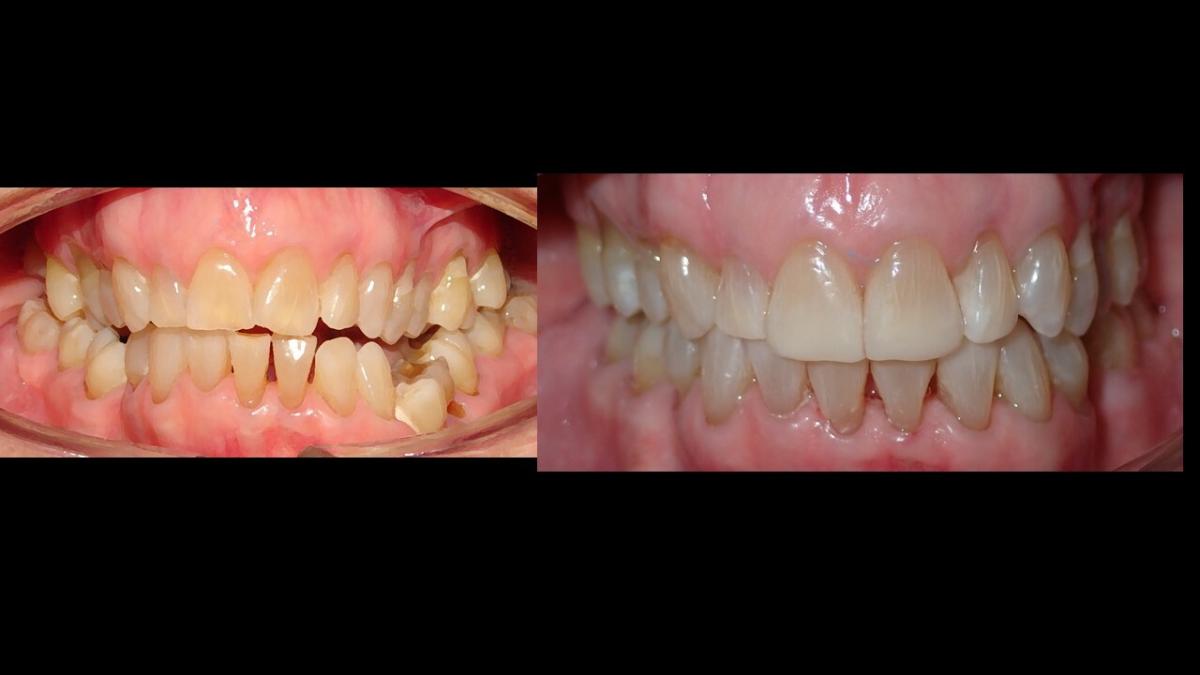

large-Cambio magico

large-Cambio labial